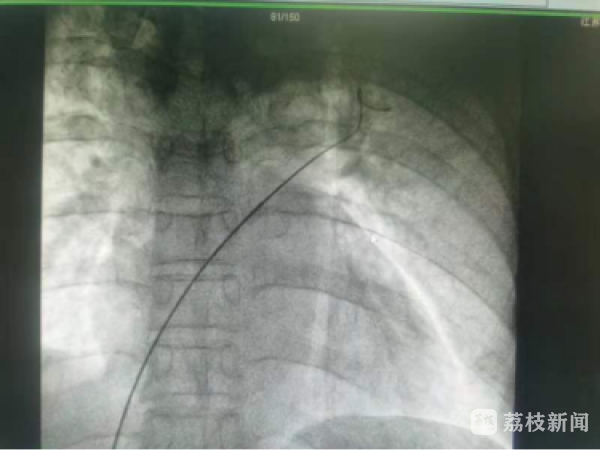

入院完善相关检查后,在沈建平主任指导、原红护理团队的协助下,主任医师龚觉晓率其介入团队,为张女士进行了“经皮卵圆孔介入封堵术”。术中通过右侧股静脉穿刺点局麻后,经静脉系统建立轨道,精确定位至卵圆孔未闭处,成功释放封堵器,主任医师陈晓栋全程提供心超监测。封堵器释放后,复查造影及心脏彩超显示位置良好,封堵器固定牢固,封堵后无残余分流。整个手术仅用了30分钟,术后患者头痛症状明显缓解,困扰多年的偏头痛终得解决,张女士如释重负。